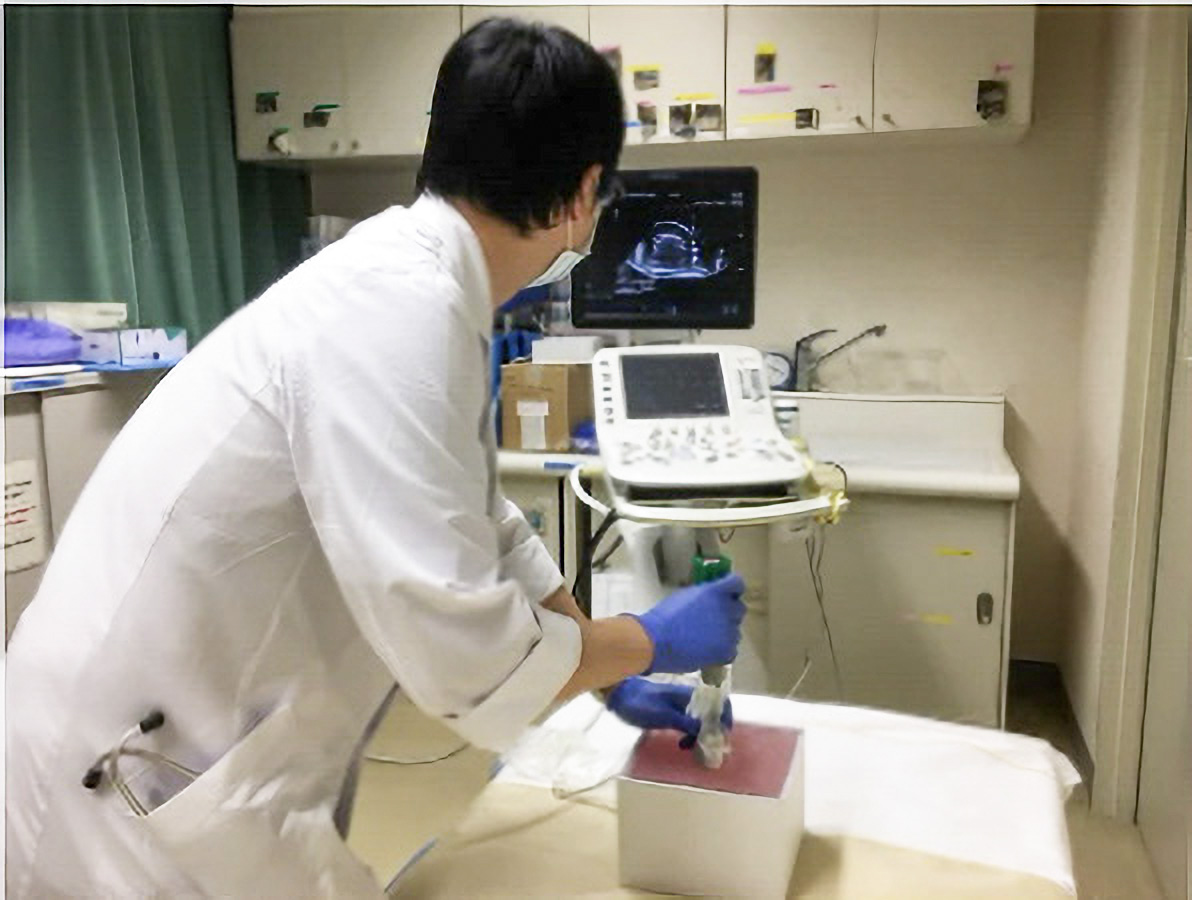

超音波ガイド経皮的針腎生検は、種々の腎臓病の診断および活動性の評価のために必要な検査ですが、出血などの合併症のリスクが高い侵襲的な技術であり、実用的なシミュレーションモデルが望まれています。

作製したモデルは、超音波下で腎臓の皮質・髄質に該当する部分のコントラストは実際の腎臓のものに類似しており、針穿刺の際にモデル内に針が侵入する様子が超音波下で観察可能です。本モデルの検証のため、岡山大学病院の腎生検経験20例未満の研修生10名に腎生検模擬を実施し、腎生検経験20例以上の腎生検に熟達した腎臓内科医20名がその様子を観察あるいは模擬を実施しました。また、腎生検模擬後に全参加者にアンケート調査を実施しました。その結果、90%の研修生が今回の腎生検模擬によって患者への腎生検に対する不安が軽減されると回答しました。

作製したモデルは、超音波下で腎臓の皮質・髄質に該当する部分のコントラストは実際の腎臓のものに類似しており、針穿刺の際にモデル内に針が侵入する様子が超音波下で観察可能です。本モデルの検証のため、岡山大学病院の腎生検経験20例未満の研修生10名に腎生検模擬を実施し、腎生検経験20例以上の腎生検に熟達した腎臓内科医20名がその様子を観察あるいは模擬を実施しました。また、腎生検模擬後に全参加者にアンケート調査を実施しました。その結果、90%の研修生が今回の腎生検模擬によって患者への腎生検に対する不安が軽減されると回答しました。